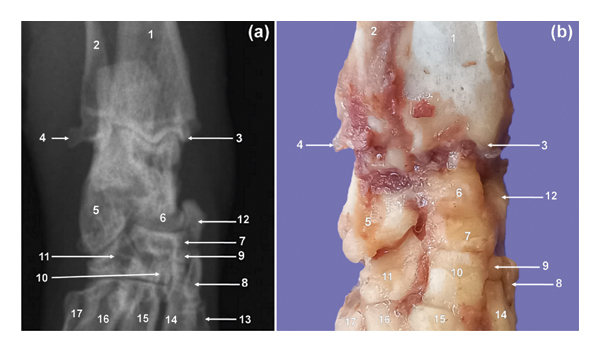

3.4. Tarsus

Seven bones were visualised and organised in three rows specifically; the proximal, middle, and distal rows (Figure 4). The calcaneus and talus bones were included in the proximal row (Figure 4). The largest bone, calcaneus, was situated plantarly and laterally to the talus (Figures 4 and 5). The latter stood the second in size (Figure 4). The middle row contained the third largest bone, the central (Figure 4). The distal row (Figure 4) consisted of tarsal (T) bones I–IV. Distally, the central bone had three more or less flat articular facets for articulation with the TII–IV (Figure 4). Medially, the central articulated with the tarsal sesamoid bone (Figure 4). Plantarly, it presented a boat-shaped tuberosity lengthened proximodistally. The TIV was the largest, whereas the TII was the smallest in the distal row. The furthermost medial bone, TI, was the third largest (Figure 4).

3.5. Metatarsal Bones and Digits

Metatarsal (MT) bones I–V were visualised. The MTI was rudimentary without phalanges whereas MTII–V were fully developed with widely spread digits. The former had a greater plantar deviation from MTII–V. The MTV was directed mediolaterally. Each of the digits II–V presented three phalanges, namely, the proximal (PI), middle (PII), and distal (PIII) phalanges (Figure 5(a)). The MTI was visualised superimposed on the MTII on the PlD view (Figure 5(a)).

3.6. Sesamoid Bones

The patella had a sharp and extended apex (Figure 6). The former had a tuberosity on the cranial surface (Figure 6(a)). The tuberosity of the patella was seen as an area of increased bone opacity on the ML view (Figure 6(a)). The patella was poorly visualised on the CdCr view of the stifle as a result of its superimposition on the distal third of the body of the femur (Figure 6(b)). A tarsal sesamoid bone was visualised in all cane rats (Figures 4 and 5). The tarsal sesamoid bone appeared comma shaped on the PlD view (Figure 4). Lateral and medial sesamoid bones of the gastrocnemius muscle (lateral and medial fabellae) were seen in all animals (Figure 6). The two fabellae were visualised superimposed on the ML view (Figure 6(a)). Each metatarsophalangeal joint of digits II–V had paired proximal sesamoid bones (Figure 5(a)). In addition, each distal interphalangeal joint of digits II–V had a distal sesamoid bone (Figure 5(b)). The mineralized sesamoid bone for the popliteal muscle was not seen (Figure 6).